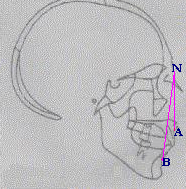

Presenta una calota prominente con occipital y frontal redondeados.

Arcos cigomaticos verticales; inclinación de incisivos superiores; barbilla en retroceso; ángulo escarpado de la mandíbula.; ANB aumentado ; Prognatismo maxillar.